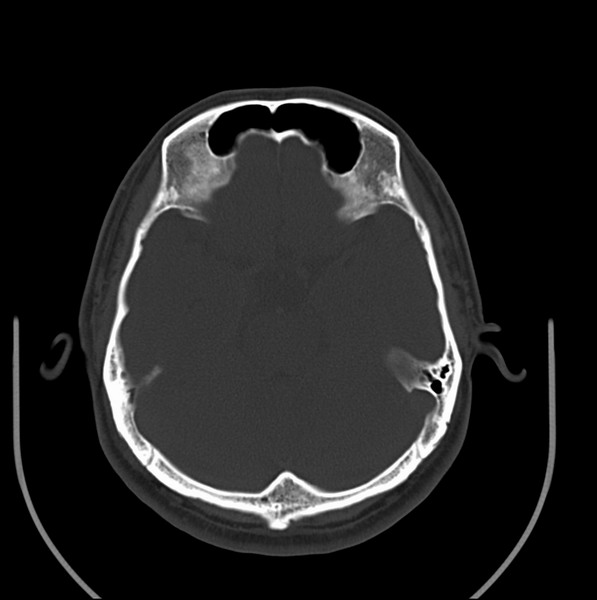

男、30、发现鼻咽部肿瘤侵犯海绵窦,未发现明显淋巴肿。请问国内那家医院治疗鼻咽部肿瘤最好?手术以何种方式为主?病灶可否全部切除?急切期待的大家的帮助。

扫描示鼻咽腔不对称,中度狭窄,右侧咽隐窝消失,局部软组织肿块,鼻咽右侧壁增厚形成肿块,突入鼻咽腔,肿块平扫呈等密度,肿块向深部侵润,右侧翼内外肌受侵,右侧咽旁间隙变窄;向后生长,头长肌界线欠清,向后上生长侵犯同侧颈动脉鞘区。双侧海绵窦增宽,内见软组织影与鼻咽部肿块相连。考虑鼻咽癌。鼻咽癌主要是放射治疗,且效果较好;到当地有治疗设备较大医院治疗即可。